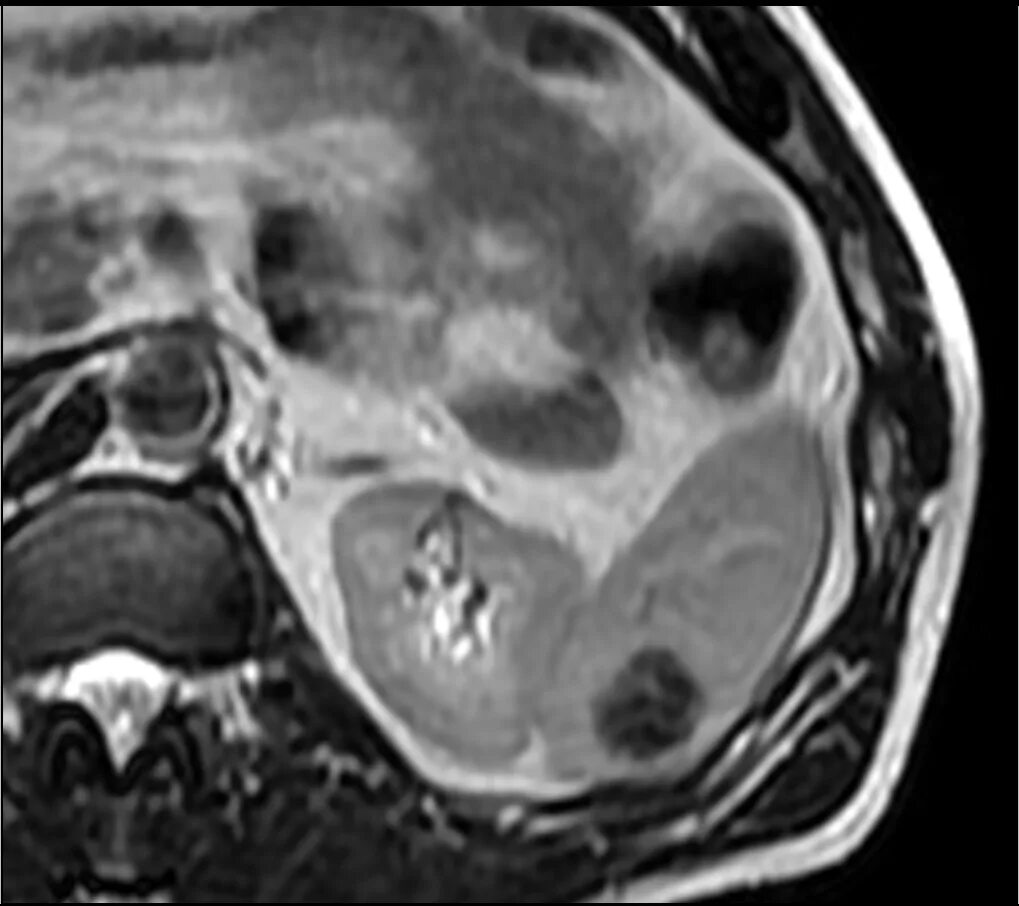

Объемные кистозные образования